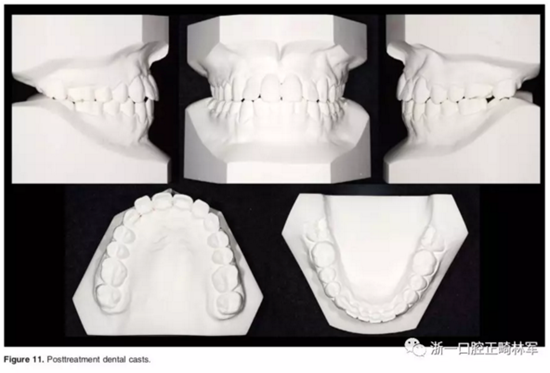

治療40個月后,3顆阻生牙位置已靠攏,繼續(xù)進行排齊。使用高轉(zhuǎn)矩托槽及帶L型曲的0.019*0.025-inch Beta鈦絲對側切牙進行轉(zhuǎn)矩控制,再在雙頜使用0.019*0.025-inch不銹鋼絲進行排齊。矯治結束后,去除托槽、弓絲,雙頜前牙區(qū)粘接保持器。

口外相:前牙易位、阻生均得以正確糾正,牙周組織健康。

口內(nèi)相及模型:I類尖牙、磨牙關系,覆合、覆蓋正常;中切牙與側切牙間有輕微的轉(zhuǎn)矩差;牙齦外形可;此外,在治療期間病人的口腔衛(wèi)生不夠良好,導致幾顆牙齒出現(xiàn)了齲病。